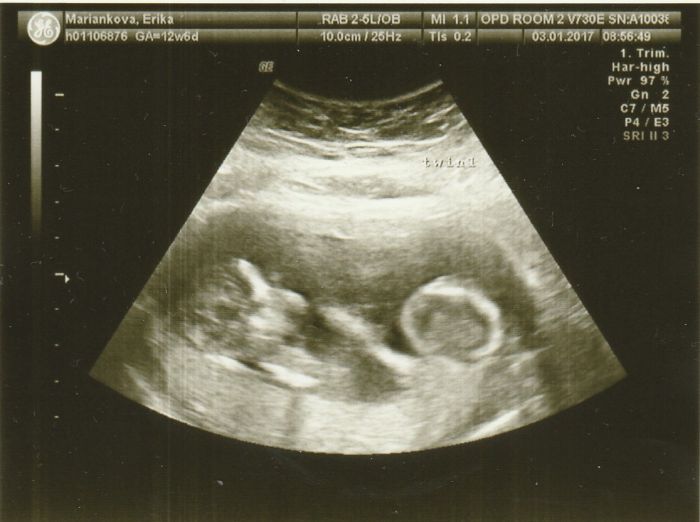

[967603] Som uz davala davnejsie, ale pridam teda este raz

Seiko krásné fotecky,hlavně ta druhá kde jsou obě miminka

je to krásné to takhle vidět